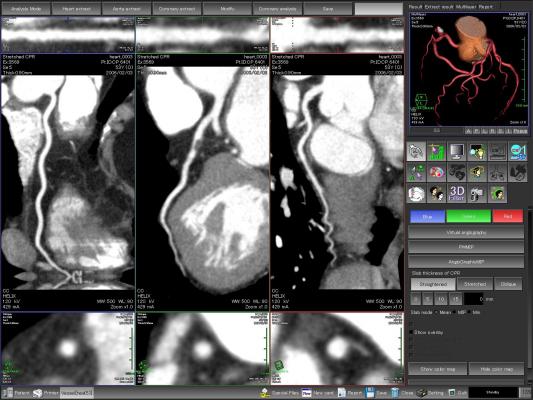

"CCTA is an excellent diagnostic modality to noninvasively depict the coronary wall and identify atherosclerotic lesions," said study author Júlia Karády, M.D., from the MTA-SE Cardiovascular Imaging Research Group, Heart and Vascular Center at Semmelweis University in Budapest, Hungary. "Furthermore, we're able to characterize plaques and differentiate between several types. Prior studies used cardiovascular risk factors — like high cholesterol levels — and cardiovascular outcomes to study the effects of alcohol, but our study is unique in that we analyzed both drinkers and non-drinkers using CCTA, which may shed some light on how alcohol may or may not contribute to the development of fatty plaques in the arteries of the heart."

The researchers studied 1,925 consecutive patients referred for CCTA with suspected CAD. Information on alcohol consumption habits was collected using questionnaires about the amount and type of alcohol consumed. Using an in-house reporting platform that contained the patients' clinical and CCTA data, researchers were able to assess the relationship between atherosclerosis, clinical risk factors and patient drinking habits.